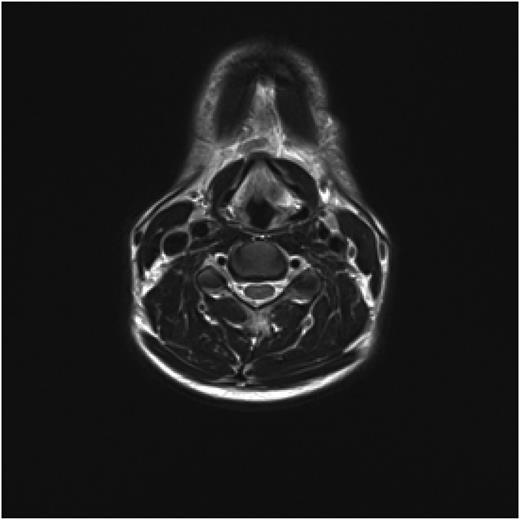

Post treatment with CO2 laser, the patient underwent a T1 weighted magnetic resonance imaging (MRI) with gadolinium of the neck. The imaging demonstrated an abnormal soft tissue density in the left supraglottic region (Figs 3 and 4). The low intensity lesion was 9 × 4 mm in size and caused distortion of the left aryepiglottic fold and minor airway narrowing. The findings on MRI suggested the persistence of disease.

Axial view of MRI neck demonstrating soft tissue abnormality in the left supraglottic area.

The role of radiological investigations is mainly supportive of the diagnosis. Laryngeal amyloidosis appears as an intermediate signal on T1 weighted MRI scan and low signal intensity on T2 weighted MRI scans similar to that of skeletal muscle. This is because protein fibrils of amyloid deposits lie in the form of parallel sheets similar to the organization of skeletal muscle fibres, therefore, can only be used in assisting a clinical and histopathological diagnosis of amyloidosis [4,7].